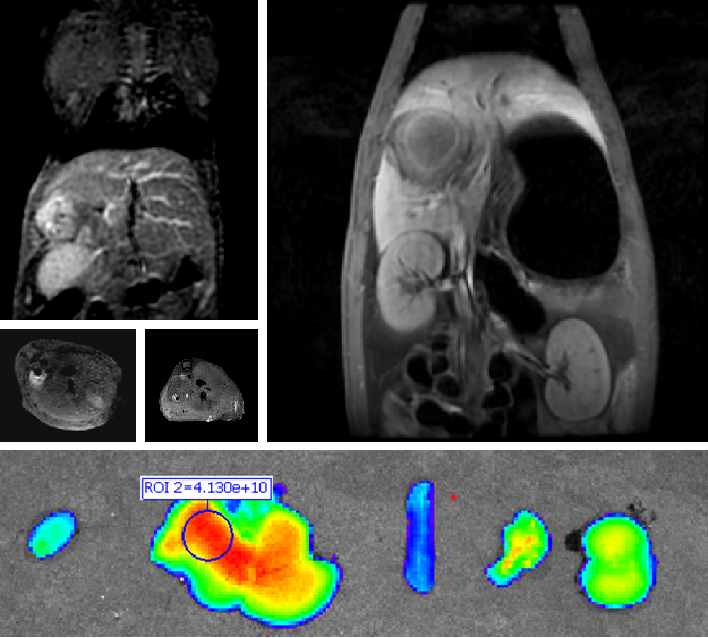

双模态造影剂PL002

PL002是浙江普利药业有限公司研发的荧光/磁共振双模态造影剂,开发荧光/磁共振双模态造影剂成为提高原发性肝癌手术效率的有效方案。双模态造影剂的荧光成像能力可用于肝癌术中荧光导航,而磁共振增强能力可用于在术前判断肝脏代谢能力,推测肿瘤及肝脏对造影剂的摄取情况,提高肿瘤诊断精度,降低术前规划难度。

PL002相较于吲哚菁绿具有明显优势。目前吲哚菁绿在临床使用中存在给药到手术时间不确定的问题,可能造成病灶与正常组织对比度不足,影响术中的病灶的判断,PL002采用独特的钆络合物与荧光分子共价键结合的分子结构设计,这种设计能够让医生在术前通过磁共振成像确定造影剂在病灶中的聚集情况,进而针对患者个体情况来对手术时间进行规划。同时,由于PL002体内更为稳定,在荷瘤小鼠模型中同等条件下荧光成像效果维持时间长于现有荧光造影剂,也保证了其在临床应用中具有更宽的手术窗口。

使用双模态造影剂可以为手术医生提供更加丰富的诊断信息,降低术中的决策压力,避免过度切成,增加发现微小病灶的可能性,最终实现患者的全面获益。此外,相较于传统荧光造影剂,PL002的安全性更高、体内更为稳定,成像效果更佳,为其临床使用提供了有效的支持。